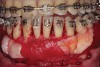

Fig 1. Preoperative SFOT. No loss of attachment, but thin dentoalveolar bone phenotype noted clinically.

Figure 1